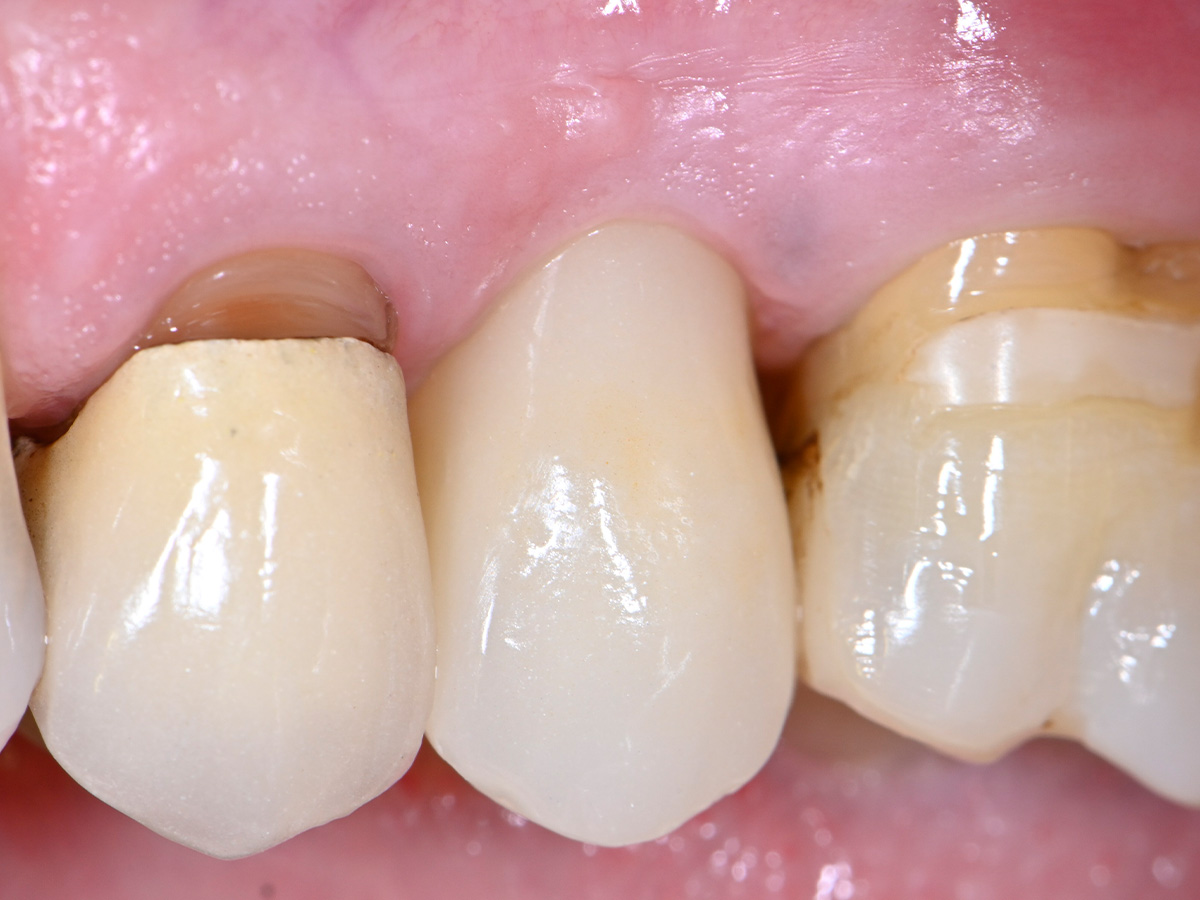

Abbildung 2

Klinische Ausgangssituation